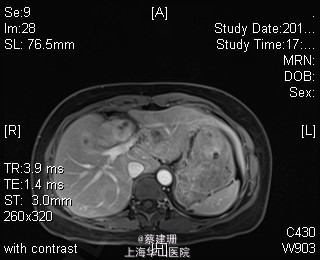

主诉:平滑肌肉瘤、肝转移癌术后,发现肝多发转移2月余。 现病史:患者3年前外院检查发现后腹膜肿瘤,外院行后腹膜肿瘤切除术后,术后病理为:平滑肌肉瘤,2013年12发现肝左叶转移癌,外院行肝左叶肿瘤切除术,术后病理为:梭行平滑肌肉瘤。2月余前患者复查发现肝脏多发转移,2015-4月肝脏MRI:肝脏多发转移。现患者无恶心、呕吐,无呕血、黑便,无皮肤巩膜黄染,无剧烈腹痛发作。现为进一步诊治收住入院。

查体:锁骨上淋巴结未扪及肿大;腹部平坦,可见陈旧性手术疤痕。未见肠型、胃型蠕动波,腹软,无压痛及反跳痛,无肌卫,肝脾肋下未及。Murphy’s 征(-),肝区叩击痛(-),肾区叩击痛(-);移动性浊音阴性。 辅查:2015-4月肝脏MRI:肝脏多发转移。

诊断 :1、多发肝转移癌 2、后腹膜平滑肌肉瘤术后 3、肝转移癌术后 处理:取右侧肋缘下切口,左侧延长,逐层切开进腹,探查腹腔:见上腹部粘连,仔细游离上腹部腹腔粘连,探查见无腹水,胃、肠、胰、脾及盆腔脏器未及异常,腹腔未见明显转移结节;肝脏无硬化。肝门淋巴结无肿大,门静脉主干无栓子。肿瘤多枚,最大两枚位于肝右叶VI段,肿瘤大小约7*6*5cm。V段肿瘤直径约5cm。左内叶肿瘤多枚,直径0.5-4cm,紧贴第一肝门。左外叶肿瘤多枚,直径1-3cm,肿块质韧,边界尚清,有包膜。术中诊断为转移性肝癌,决定行左半肝切除,肝右叶特殊肝段切除。